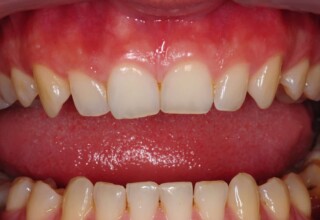

Όψεις Πορσελάνης

Οι όψεις πορσελάνης είναι ο καλύτερος τρόπος αντιμετώπισης αισθητικών προβλημάτων στην πρόσθια περιοχή του στόματος. Συνδυάζουν συντηρητική αφαίρεση οδοντικής ουσίας και πολύ υψηλή αισθητική απόδοση. Στο παρακάτω εκτεταμένο περιστατικό υπήρχαν: παλαιά σφραγίσματα, δυσχρωμίες, κακό σχήμα και μήκος δοντιών, κακή αναλογία δοντιών-ούλων. Έγινε προσεκτικός εργαστηριακός σχεδιασμός σε εκμαγεία απ’όπου προέκυψαν προσωρινές όψεις που τοποθετήθηκαν στο στόμα για δοκιμή και διορθώσεις. Όταν οριστικοποιήθηκαν οι μετατροπές, οι προσωρινές χρησιμοποιήθηκαν σαν οδηγός για τις μόνιμες. Οι πέντε μόνιμες όψεις πορσελάνης που κατασκευάστηκαν για τα πέντε πρόσθια δόντια της άνω απεκατέστησαν σχεδόν άψογα την αισθητική εμφάνιση της ασθενούς.

Αρχική εμφάνιση

Τελική εμφάνιση